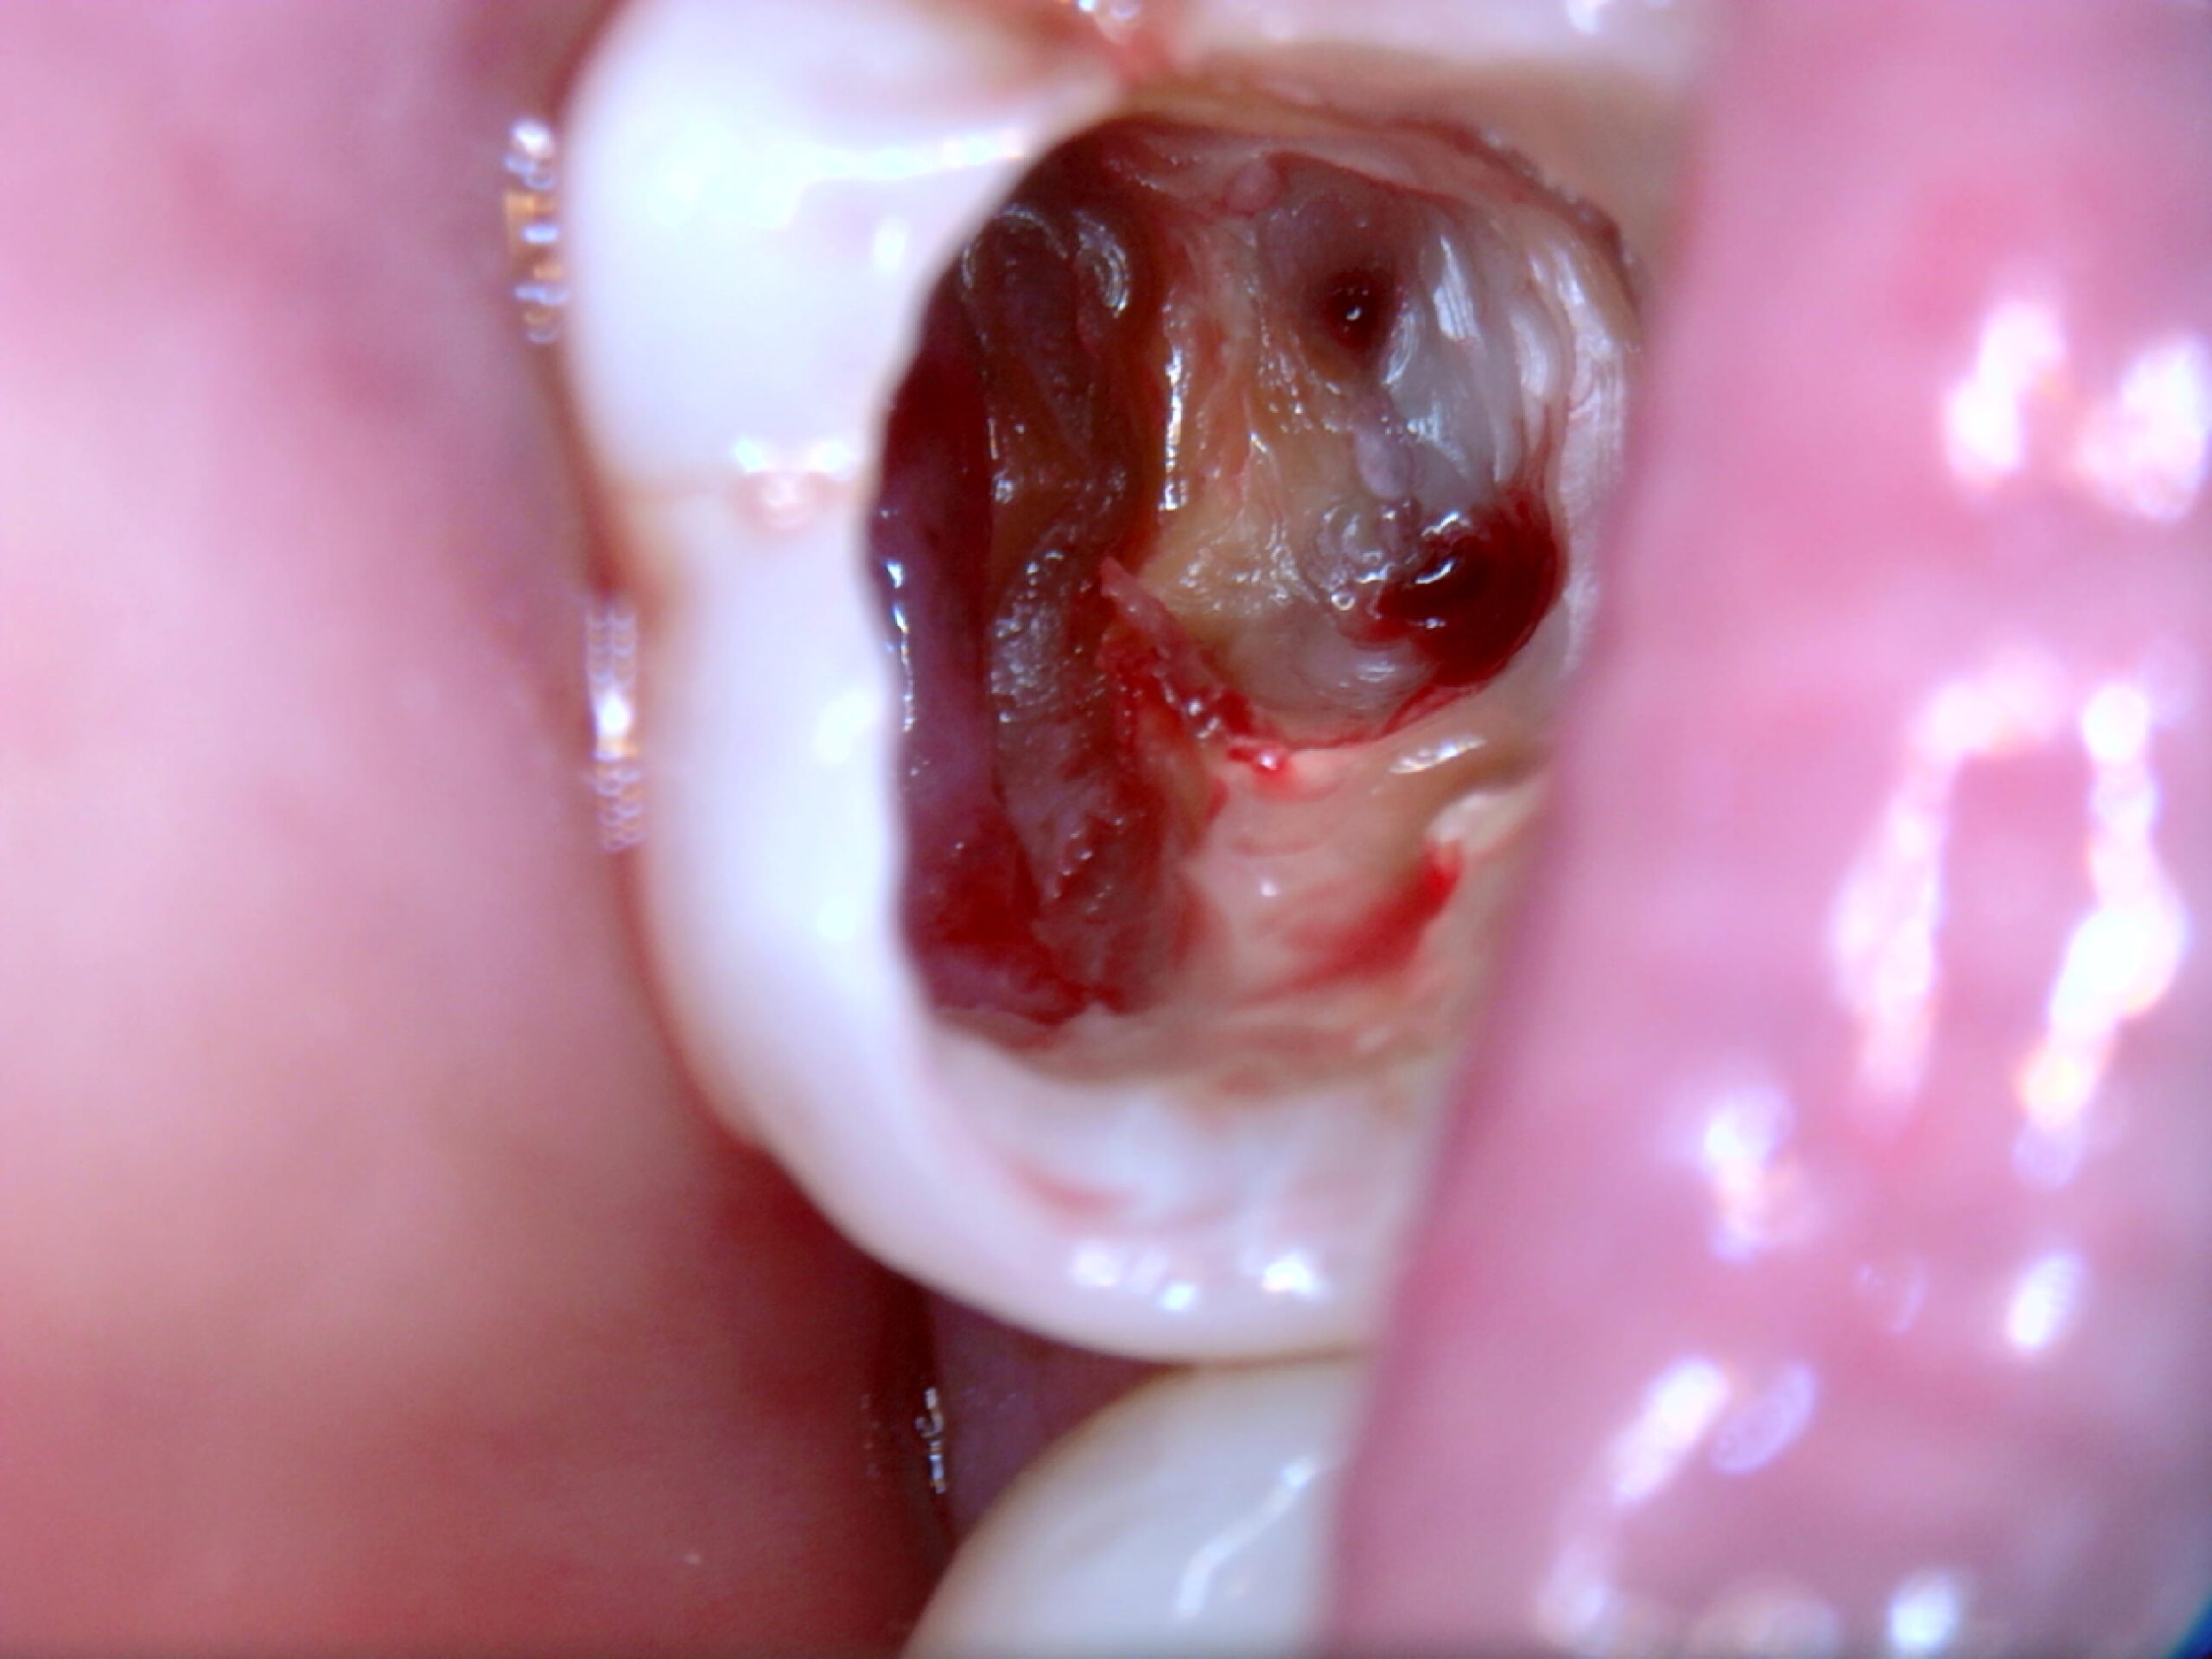

1. Enxergar o que o olho humano não vê

Trincas, fraturas e infiltrações ficam extremamente evidentes com a ampliação da SkyCam.

Exemplos reais de uso da SkyCam na Endodontia

Detalhamento preciso de microestruturas

Imagens altamente nítidas para avaliar a verdadeira extensão da lesão.

Dor sem causa aparente? A SkyCam revela trincas e infiltrações invisíveis.